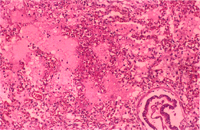

三 、 組織病變: 1.

肝臟:實質組織內可見局灶性壞死(圖 3),壞死區內膽管之上皮細胞內有紅色的核內包涵體(圖4) 。

肺臟:肺泡腔內可見水腫液、實質組織局灶性壞死(圖 2),可見紅色的核內包涵體。肺門淋巴結發生局灶性壞死。

一般在豬假性狂犬病的診斷上,特徵性病變為非化膿性腦膜腦炎以及在內臟器官形成多發壞死灶伴隨著核內包涵體,根據劉等(2)所述感染假性狂犬病的豬隻其組織發生病灶的頻率以腦最多,再來依次為脊髓、會厭部、扁桃腺、胎盤、淋巴結、肝臟、腎上腺、肺以及脾臟;而核內包涵體在各組織出現之頻率,則以扁桃腺(81.8%)為最高再來依次為胎盤、淋巴結、腎上腺、肺臟、會厭部以及肝臟 (34.8%),另有少數病例在胃與唾液腺發現核內包涵體。本病例為一特殊病例,在肝臟壞死灶周圍沒 有看到核內包涵體,但在壞死組織旁的膽管上皮細胞內卻可見到紅色的核內包涵體, 所以日後在豬假性狂犬病的診斷上除了要觀察上述常見到病灶的組織外,也應留意 一下壞死灶周圍組織的變化。 (二) 參考文獻: 1.